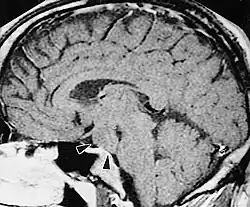

Hamartoma podwzgórza

Hamartoma podwzgórza (ang. hypothalamic hamartoma, HH) – wrodzony, nienowotworowy guz podwzgórza, objawiający się klinicznie triadą objawów: napadami śmiechu (ang. gelastic seisures), przedwczesnym dojrzewaniem płciowym i opóźnieniem rozwoju. Niekiedy, w związku z uciskiem guza na skrzyżowanie wzrokowe, pojawiają się zaburzenia widzenia.